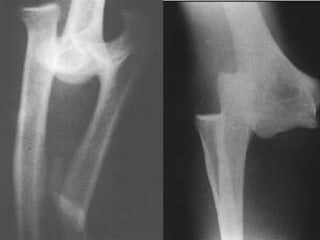

LUXAÇÃO DO COTOVELO

LUXAÇÕES DO COTOVELO

•O Cotovelo é articulação mais estável do corpo

•Porém a luxação é comum

•A cicatrização da cápsula ocorre mesmo com

movimentos ativos

•Mecanismo: trauma indireto (queda)

•Mais comum: posterior

•Quadro Clínico: deformidade com perda da relação

entre os epicôndilos e o olécrano

•Rx: perda da congruência articular do cotovelo

•Tratamento

–Redução incruenta

–Imobilização por 1 a 3

semanas

–Ganho de Amplitude

de Movimentos

precoce